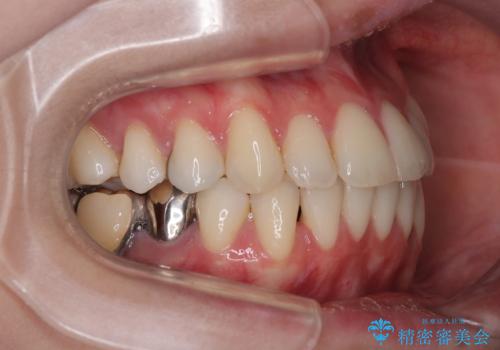

- 上下前歯のデコボコとクロスバイトを気にして来院された患者様です。

治療済みの処置歯が多いため、インビザラインを用いて矯正治療を行うこととしました。

下顎臼歯部にブリッジが装着されており、移動不可のため、IPR(歯と歯の間を削る)と歯列全体を拡大させることで、歯並びを整えていくこととしました。